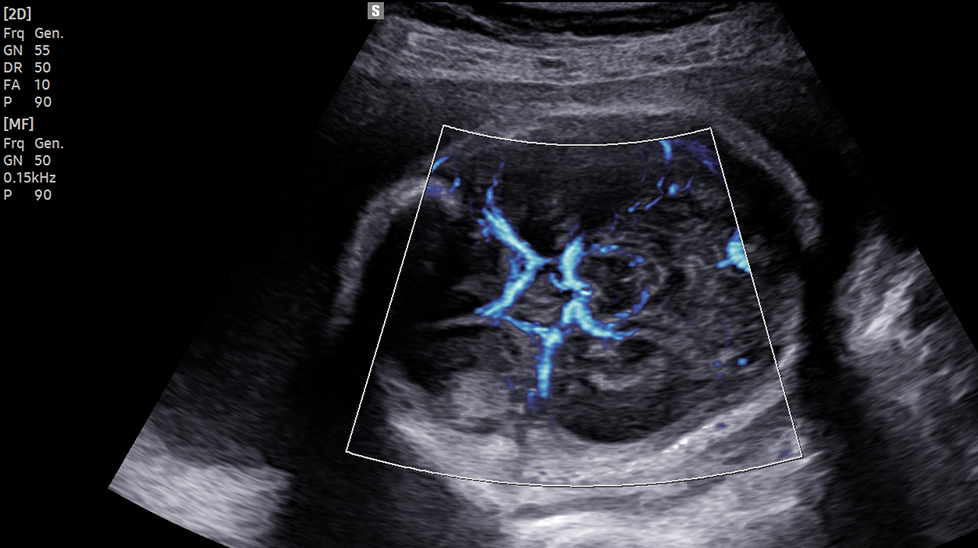

Трехмерная визуализация кровотока LumiFlow™ - это трехмерная визуализация кровотока, которая помогает интуитивно понять структуру кровотока и мелких сосудов.

на изображении: Цветная допплерография с LumiFlowTM (4-камерный вид)